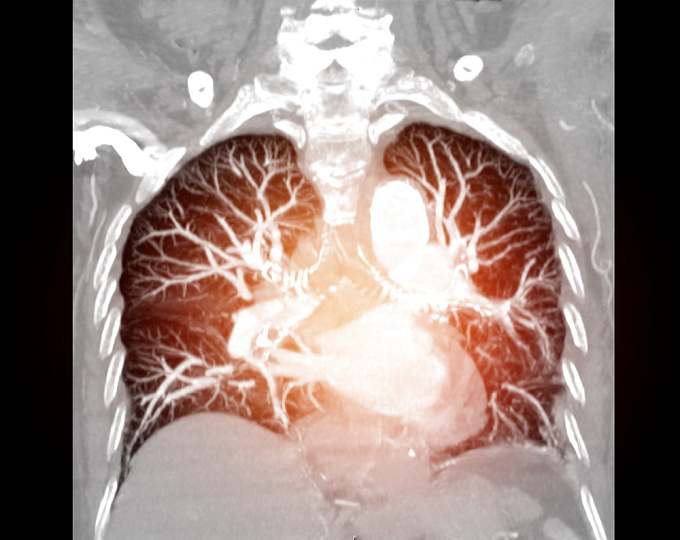

Оптимальная продолжительность антикоагулянтной терапии у пациентов с раком и легочной эмболией

Оптимальная продолжительность антикоагулянтной терапии у пациентов с раком и легочной эмболией низкого риска точно не определена.